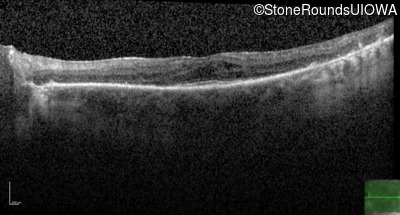

Optical Coherence Tomography - Right - 20/40 -2

Exemplar / OCT Stack